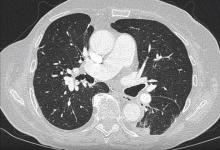

In this video, the author presents the case of a 78-year-old patient who was admitted for recurrent lung carcinoma in the left lower lobe. Three years prior, the patient was diagnosed with adenocarcinoma in the right upper lobe. The patient underwent a right upper lobectomy, wedge resection of the lower lobe, and mediastinal lymphadenectomy via right posterolateral thoracotomy. A wedge resection via posterolateral thoracotomy and chemotherapy were performed three months afterwards due to a metastatic tumor in the left lower lobe.

The author performed an extended lower lobectomy via left rethoracotomy for the recurrent tumor in the left lower lobe. Chylothorax occurred on the first postoperative day. Conservative management of chylothorax and surgical intervention on the left lobe (re-rethoracotomy for the ligation of the thoracic duct) failed to provide improvement. The author then decided to perform a right-sided VATS clipping of the thoracic duct.